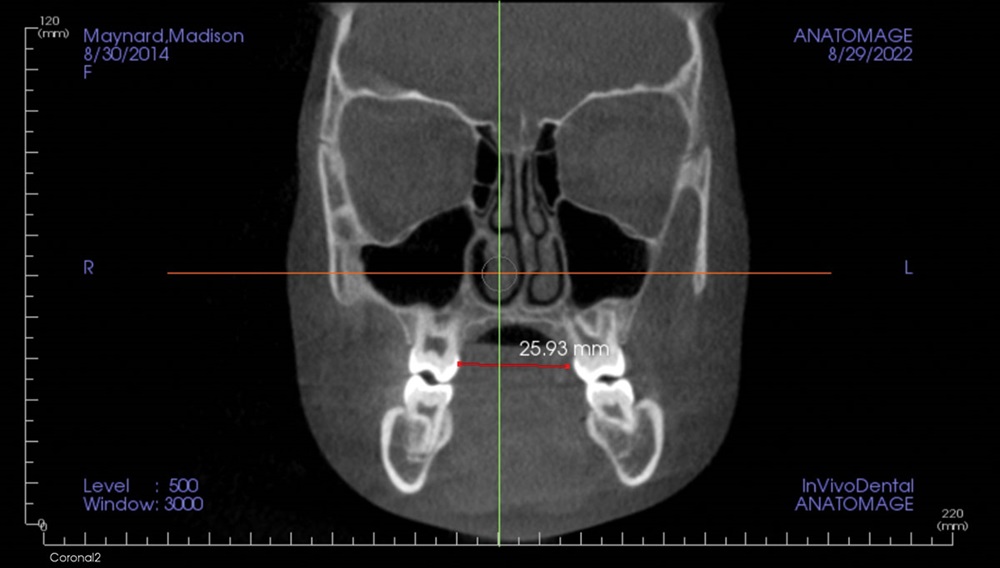

Lastly, the section screen (Fig. 16) is

again used to measure the distance between

palatal surfaces of the first upper molars. It

is also in this tab that cross-sections of the

nasal cavity are viewed to ascertain the size

and shape of the turbinates, nasal septum,

etc. This last finding and measurement is

the key to proceeding with early treatment

or medical referrals involving expansion, lingual arches and alignment of the upper

incisors with fixed appliances or aligners.

Fig. 16